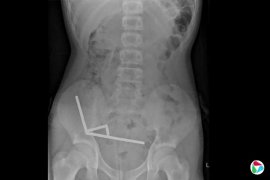

新西兰男童吞百片网购磁铁 肠道部分组织坏死

新西兰一名13岁男童吞下多达100片在Temu购买的高功率钕铁硼磁铁,必须动手术取出磁铁,部分坏死组织也得切除。 法新社报道,这名未被公布姓名的男童吞下磁铁后经历四天腹痛,被送往新西兰北岛的陶朗加医院(Tauranga Hospital)。 陶朗加医院的医生在《新西...